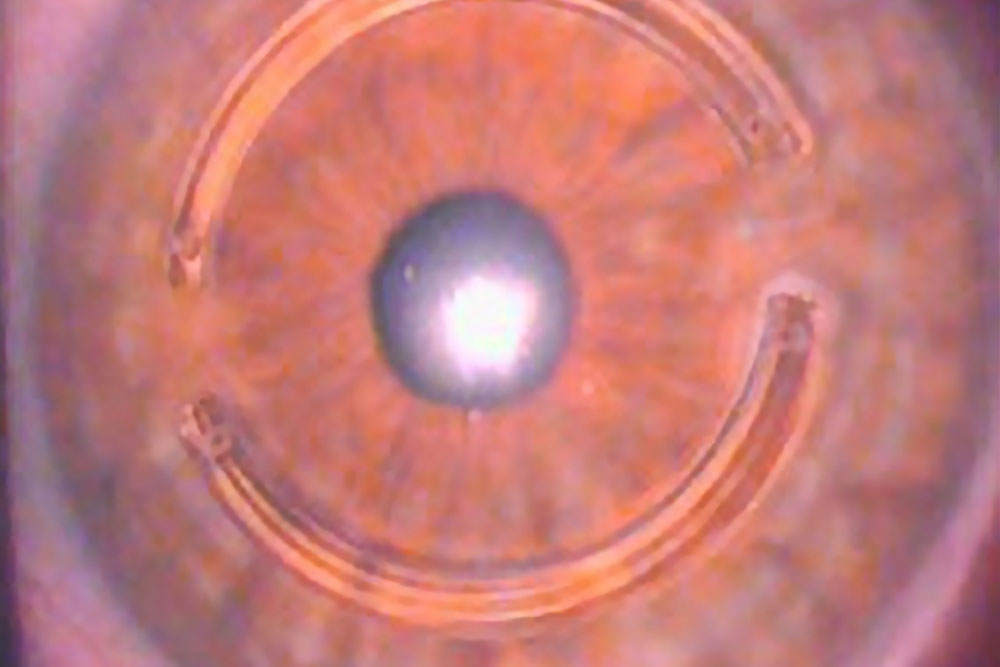

The surgery indicated in the more advanced situations, and as long as the cornea maintains its normal transparency, is the introduction of intra-stromal corneal rings (Intacs, Kerarings or Ferrara Rings). This technique consists of implanting one or more semi-circular segments of synthetic material (PMMA), in a tunnel previously created, in the thickness of the cornea.

This tunnel can be done manually, using semi-circular blades or, ideally, by the Femtosecond Laser, with which a greater accuracy is achieved in its centering and depth. For this reason, we always use laser for the surgery of the intra-stromal rings.